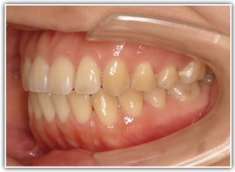

治療後(1年8ヶ月後)

良好な咬合関係が認められます。